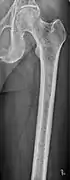

Multiple myeloma in the upper arm

The diagnostic examination of a person with suspected multiple myeloma typically includes a skeletal survey. This is a series of X-rays of the skull, axial skeleton, and proximal long bones. Myeloma activity sometimes appears as "lytic lesions" (with local disappearance of normal bone due to resorption). And on the skull X-ray as "punched-out lesions" (pepper-pot skull). Lesions may also be sclerotic, which is seen as radiodense.[47] Overall, the radiodensity of myeloma is between −30 and 120 Hounsfield units (HU).[48] Magnetic resonance imaging is more sensitive than simple X-rays in the detection of lytic lesions, and may supersede a skeletal survey, especially when vertebral disease is suspected. Occasionally, a CT scan is performed to measure the size of soft-tissue plasmacytomas. Bone scans are typically not of any additional value in the workup of people with myeloma (no new bone formation; lytic lesions not well visualized on bone scan).

Femur with multiple myeloma lesions

Same femur before myeloma lesions for comparison